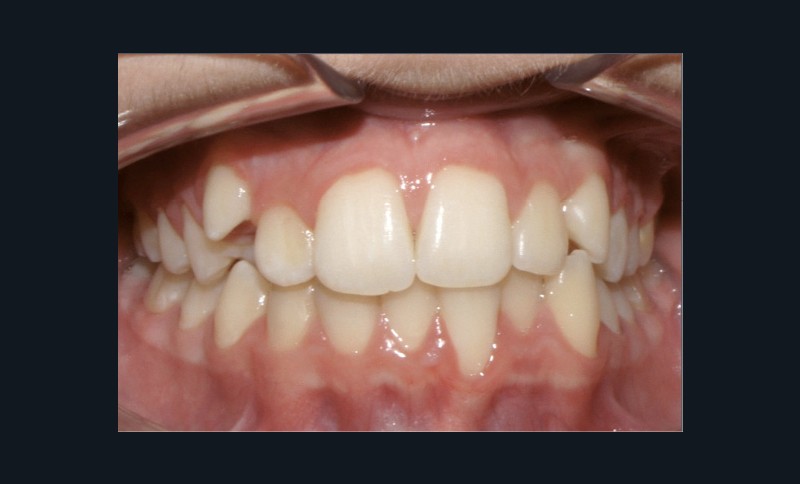

Examen endo-buccal (fig. 2a-e)

Dans le sens transversal, l’occlusion des secteurs latéraux est correcte mais on constate une discordance des médianes incisives liée à la déviation de la médiane maxillaire vers la droite et à celle de la médiane incisive mandibulaire vers la gauche.

Le recouvrement est de 2 mm.